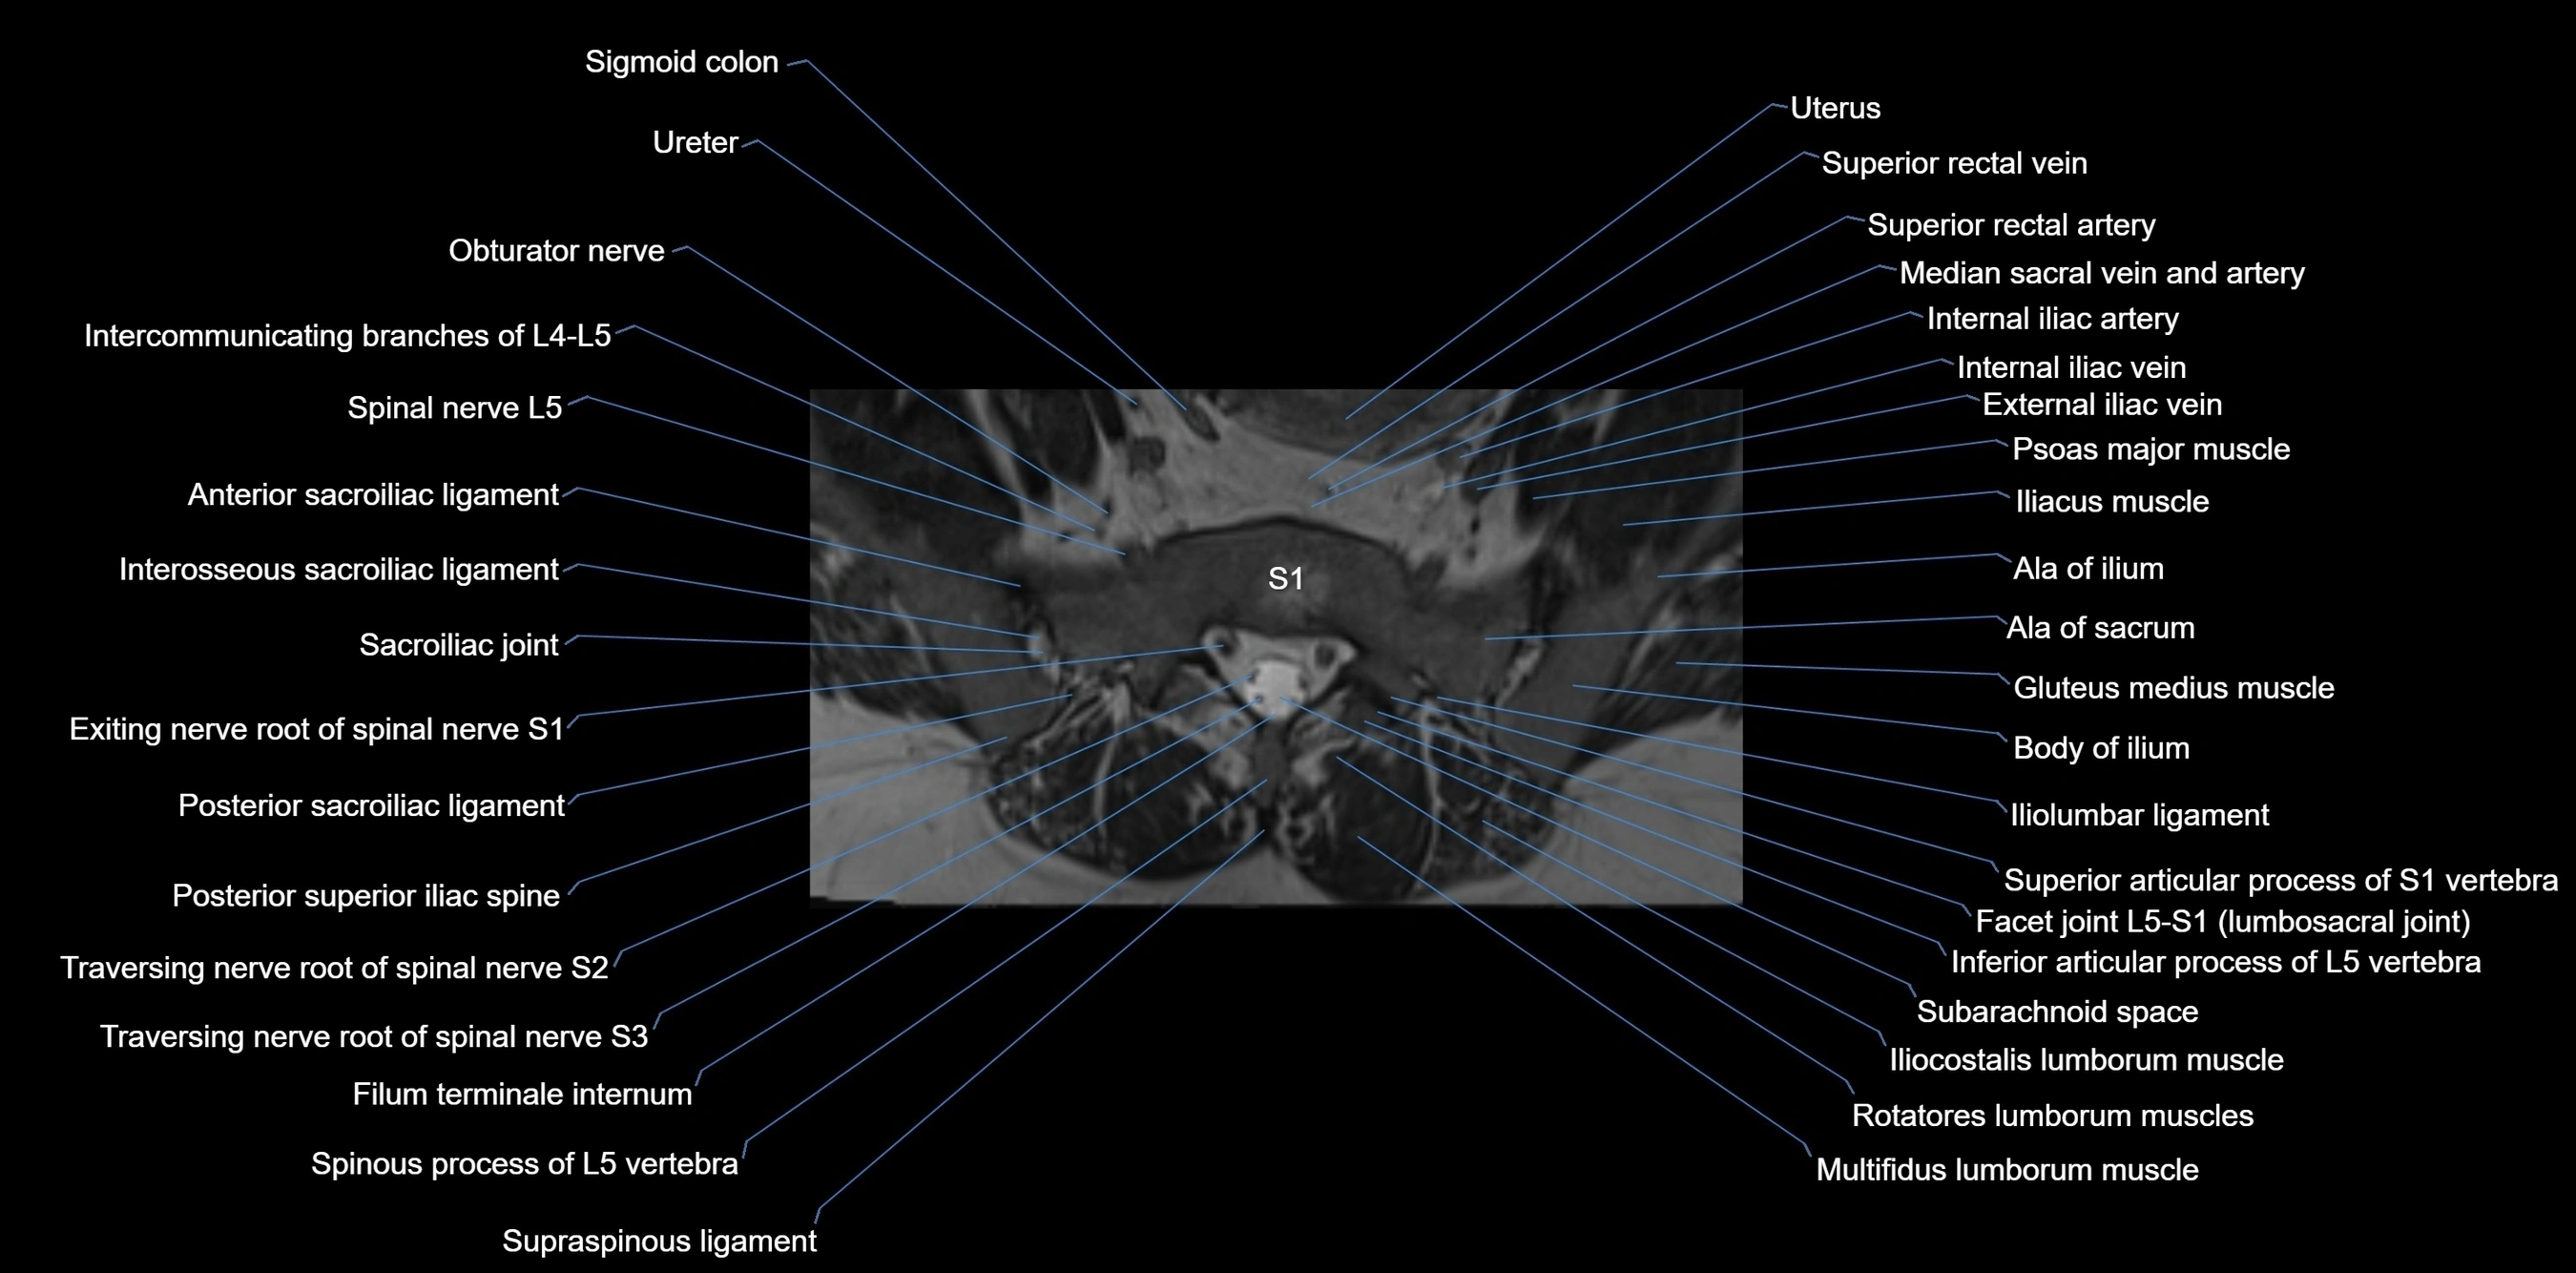

MRI image

image